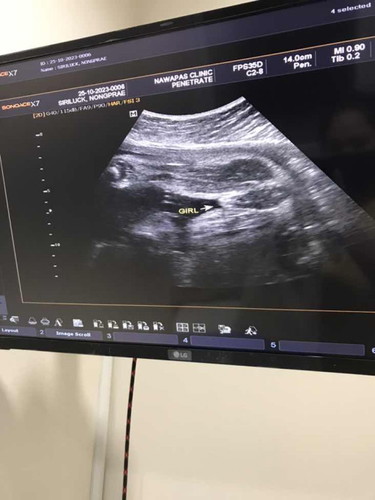

ตั้งครรภ์31วีค ไปซาวมาน้องน้ำหนัก

1485น้อยไปไหนค่ะ อยากให้แม่ช่วยดูรูปภาพน้องผู้หญิงรึชายค่ะหมอบอกผู้หญิง

ผู้หญิงค่ะ